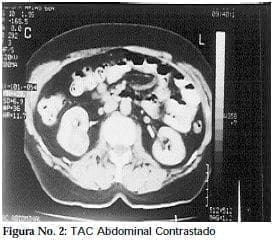

Paciente de sexo femenino de 64 años de edad, quien ingresa al servicio de urgencias, presentando intenso dolor a nivel del hipocondrio derecho. El médico de turno pensando en una patología biliar aguda solicitó interconsulta con el gastroenterólogo. Se solicitó una ecografía abdominal (figura 1), que muestra la existencia de una masa tumoral sólida a nivel del polo inferior del riñón derecho. Se solicitó un TAC contrastado que demuestra la presencia de una masa tumoral sólida sospechosa de carcinoma de célulasrenales, localizada en la cara posterior del polo inferior del riñón derecho (figura 2). El cuadro hemático, la glicemia y las cifras de creatinina son normales. La paciente tiene antecedentes de hipertensión arterial y cistitis recurrente. Los parciales de orina muestran hematuria microscópica con leucobacteriuria. Una uretrocitoscopia demostró trigonitis quística-leucoplásica y áreas aisladas de congestión en la mucosa vesical. Una urografía practicada un año atrás fue reportada como normal (figura 3), y con presencia de calcificaciones vasculares esplénicas concomitantes.